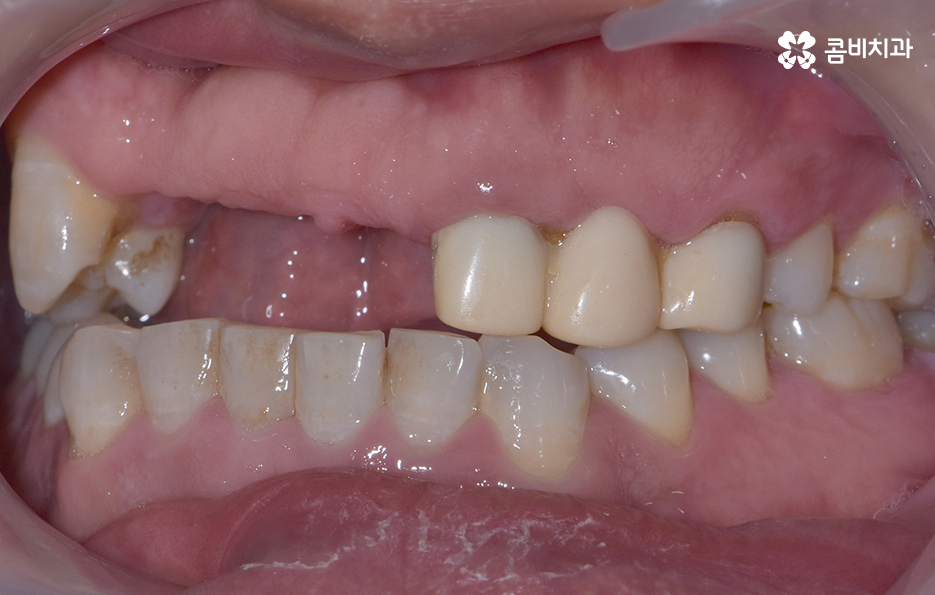

이렇게 앞니가 상실되면 심미적, 기능적 불편이 크기 때문에 많은 분들이 앞이빨 임플란트 과정을 거치게 되는데 앞니 임플란트는 어금니와는 다른 부분에서 좀더 정교한 치료가 필요하며 앞니 부위는 뼈가 얇고 심미성이 중요한 부위라는 점에서 잇몸 라인, 앞니의 각도, 심미성, 주변 치아와의 조화까지 모두 맞아야 자연스럽게 보이므로 정교한 치료의 중요성이 더 높은 부위라고 할 수 있어요

그리고 앞니는 씹는 힘이 약해 보이지만 가로 방향 힘이 많이 가해져서 임플란트에 부담을 주기 쉽고 앞니 상실의 원인이 치주염이라면 뼈가 많이 녹아 있는 경우가 많아 뼈 이식이 필수적인 상황이 자주 생기므로 앞이빨 임플란트 과정에서 주의해야 할 점들에 대해 잘 알고 접근하는 것이 중요한 거예요

또한 앞니는 잇몸의 모양이 심미성에 큰 영향을 주는데, 잇몸이 얇으면 임플란트가 비쳐 보이거나 잇몸 라인이 붕괴될 위험이 있어서 이런 경우에는 잇몸 두께를 보강하는 잇몸 이식술이 필요할 수 있으며 앞이빨 임플란트 과정 뿐 아니라 치료 후에도 잇몸 관리는 앞니 임플란트의 수명, 심미적인 유지에 있어서 중요한 요소라고 볼 수 있었어요

앞니는 사람들에 따라서 상실 원인이 다르고 현재의 잇몸 및 전신건강 상태가 다르며 특히 중년이후에는 기존의 보철물이 노후되거나 치주염으로 인해 치아를 상실하는 경우도 많기 때문에 앞이빨 임플란트 과정이라서 해서 단지 빠르게 치료하는 것만이 중요한 것이 아니라 장기적인 안정성 등을 충분히 고려한 치료 계획이 중요하므로 경험 많은 치과의사와 충분히 상의하고 정밀검진 결과를 토대로 나에게 맞는 치료 계획 그리고 사후관리까지 고려한 장기적인 유지까지 고려하여 판단하시길 바라고 있어요